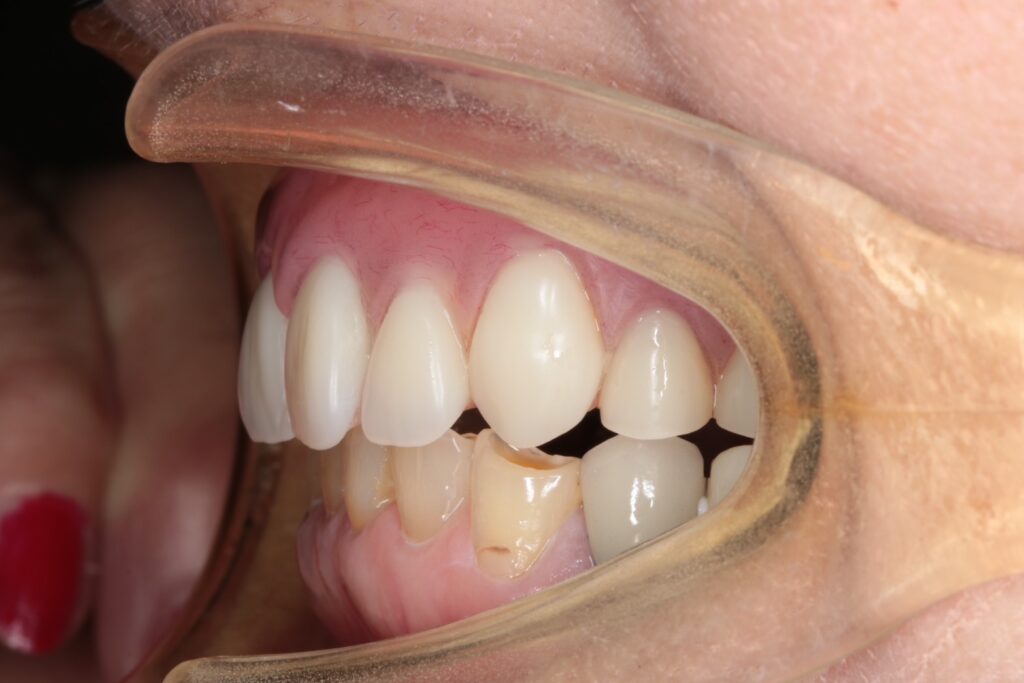

■術後の状態

治療後の写真を見ると、上下ともに大きく審美性が改善し、笑顔の印象も自然になりました。

また、噛み合わせも安定し、患者さまからは「噛めるようになって本当に嬉しい」とのお声をいただきました。